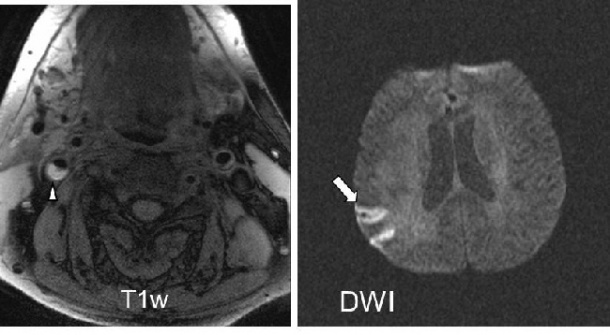

DWI-Sequenz – siehe Pfeil). Der Patient hat ein eingeblutetes und somit kompliziertes Plaque in der rechten

A. Carotis interna (siehe Pfeilspitze in der T1w Sequenz), das – obwohl es nicht stenosierend wirkt - den

Schlaganfall vermutlich ausgelöst hat.